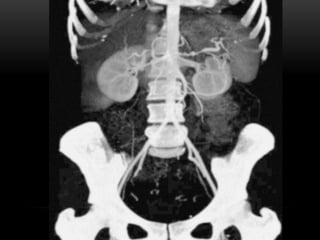

PROYECCIÓN DE MÁXIMA INTENSIDAD MIP

• Selecciona un rango de cortes bidimensionales

• Permite realzar las estructuras con mayor atenuación, facilita una visualización rápida y

efectiva de estructuras densas ( vasos contrastados y huesos)

• Este procedmiento se emplea principamente para examinar v. sang contrastados

PROYECCIÓN DE MÁXIMAINTENSIDAD MIP • Selecciona un rango de cortes bidimensionales • Permite realzar las estructuras con mayor atenuación, facilita una visualización rápida y efectiva de estructuras densas ( vasos contrastados y huesos)

• 62.

• Este procedmientose emplea principamente para examinar v. sang contrastados